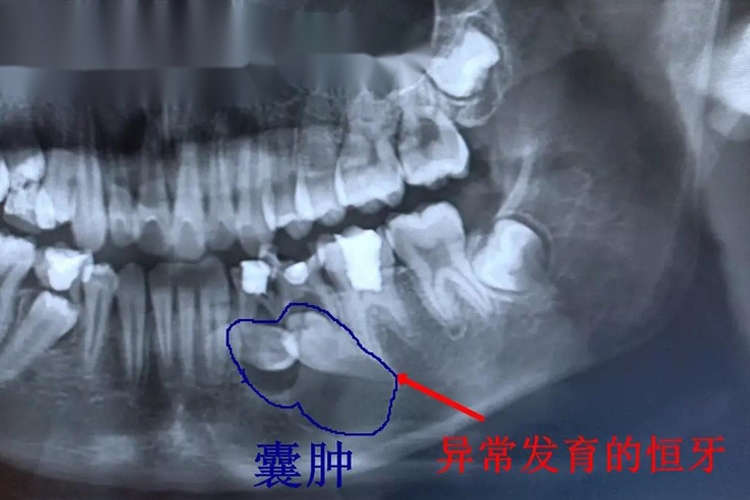

含牙囊肿

儿童含牙囊肿多发生于下颌前磨牙,较小的囊肿可仅表现为影像学改变,无明显临床症状,较大的囊肿可导致颌骨膨胀和相邻牙移位。